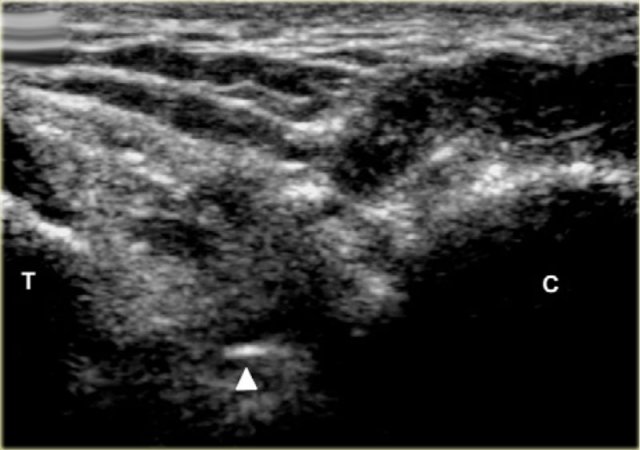

US-guided injection of the sinus tarsi at the right-hand side with a lateral approach. The transducer is held in a coronal oblique plane. The needle is introduced along the long axis of the transducer.

The sinus tarsi can easily be visualized using ultrasound.

The patient turns onto the contralateral side laying the foot to be treated with its medial surface against the table top, the lateral side of the foot being uppermost.

The transducer is held in a coronaloblique plane with regards to the foot.

The sinus tarsi is identified as a triangular space between the anterior process of the calcaneus and the talar neck.

The tip of the needle (arrow head) is seen within the cone shaped sinus tarsi, which is bordered by the talus (T) and calcaneus (C).

Depending on the degree of inflammation there may be hyperemia of the space and there may be intervening vessels visible, which one wishes to avoid. This is relatively easy, especially with colour doppler